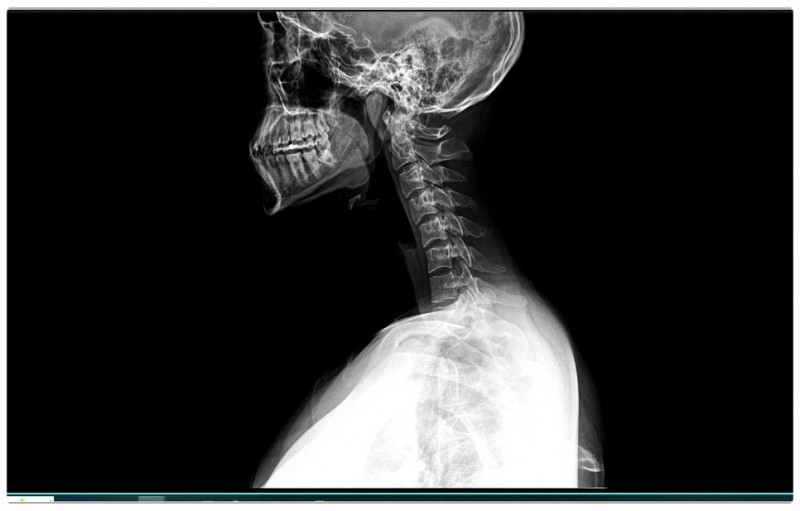

하지만 실제로는 거북목과 굽은 등이 함께 진행되는 경우가 많습니다.

특히 어깨 통증이나 팔로 방사되는 통증이 동반된다면,

몸이 이미 어떤 신호를 보내고 있다는 뜻이죠.

턱관절이 살짝 틀어지면 바로 아래 목뼈 1번, 2번이 영향을 받습니다.

이 부분에서 균형이 무너지면 목은 앞으로 빠지고,

굽은 등이 만들어지죠.